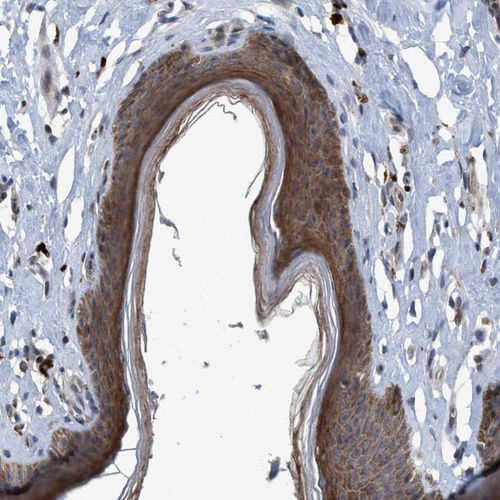

Immunohistochemical staining of human cerebellum shows strong cytoplasmic and membranous positivity in Purkinje cells.